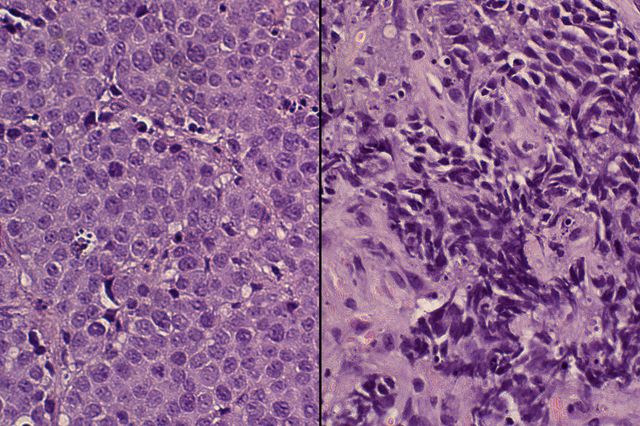

With patients’ consent, the researchers obtained non-cancerous prostate basal cells — which contain prostate stem cells that can regenerate all other types of prostate cells — from men who underwent prostate surgery at the Ronald Reagan UCLA Medical Center. They then added a gene called MYCN to those cells. MYCN produces a protein called N-Myc, which is known to play a role in several types of aggressive cancer. In prostate cancer specifically, it seems to turn less aggressive prostate cancer cells into the cancer stem cells that form the aggressive neuroendocrine prostate cancer tumors.

Next, the researchers transplanted the basal cells with the added MYCN genes into mice. Those cells with elevated N-Myc levels grew into neuroendocrine prostate cancer tumors, said Dr. John Lee, the study’s first author and a clinical instructor in the Division of Hematology Oncology at the UCLA David Geffen School of Medicine.